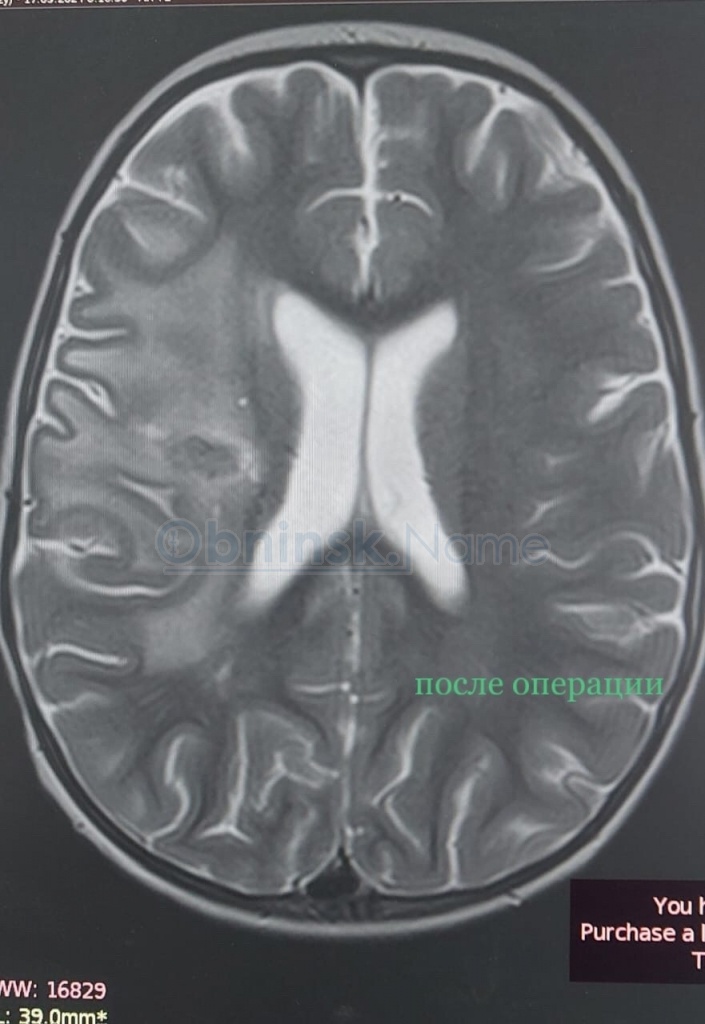

После незначительной травмы головы у него развились судороги, и состояние быстро ухудшалось. Обследование выявило у малыша абсцесс, который располагался глубоко в толще правого полушария мозга. Ситуация осложнялась тем, что очаг находился рядом с очень важными зонами мозга, и делать открытую полноценную операцию было рискованно.

— Детский нейрохирург Илья Балбеко с коллегами из областной больницы смогли удалить абсцесс из минидоступа в 1 см. Операция проводилась с использованием специализированного оборудования — нейронавигатора и длилась несколько часов. Но, несмотря на все трудности, всё закончилось более чем благополучно, — рассказали в больнице.

Сейчас малыша готовят к выписке.